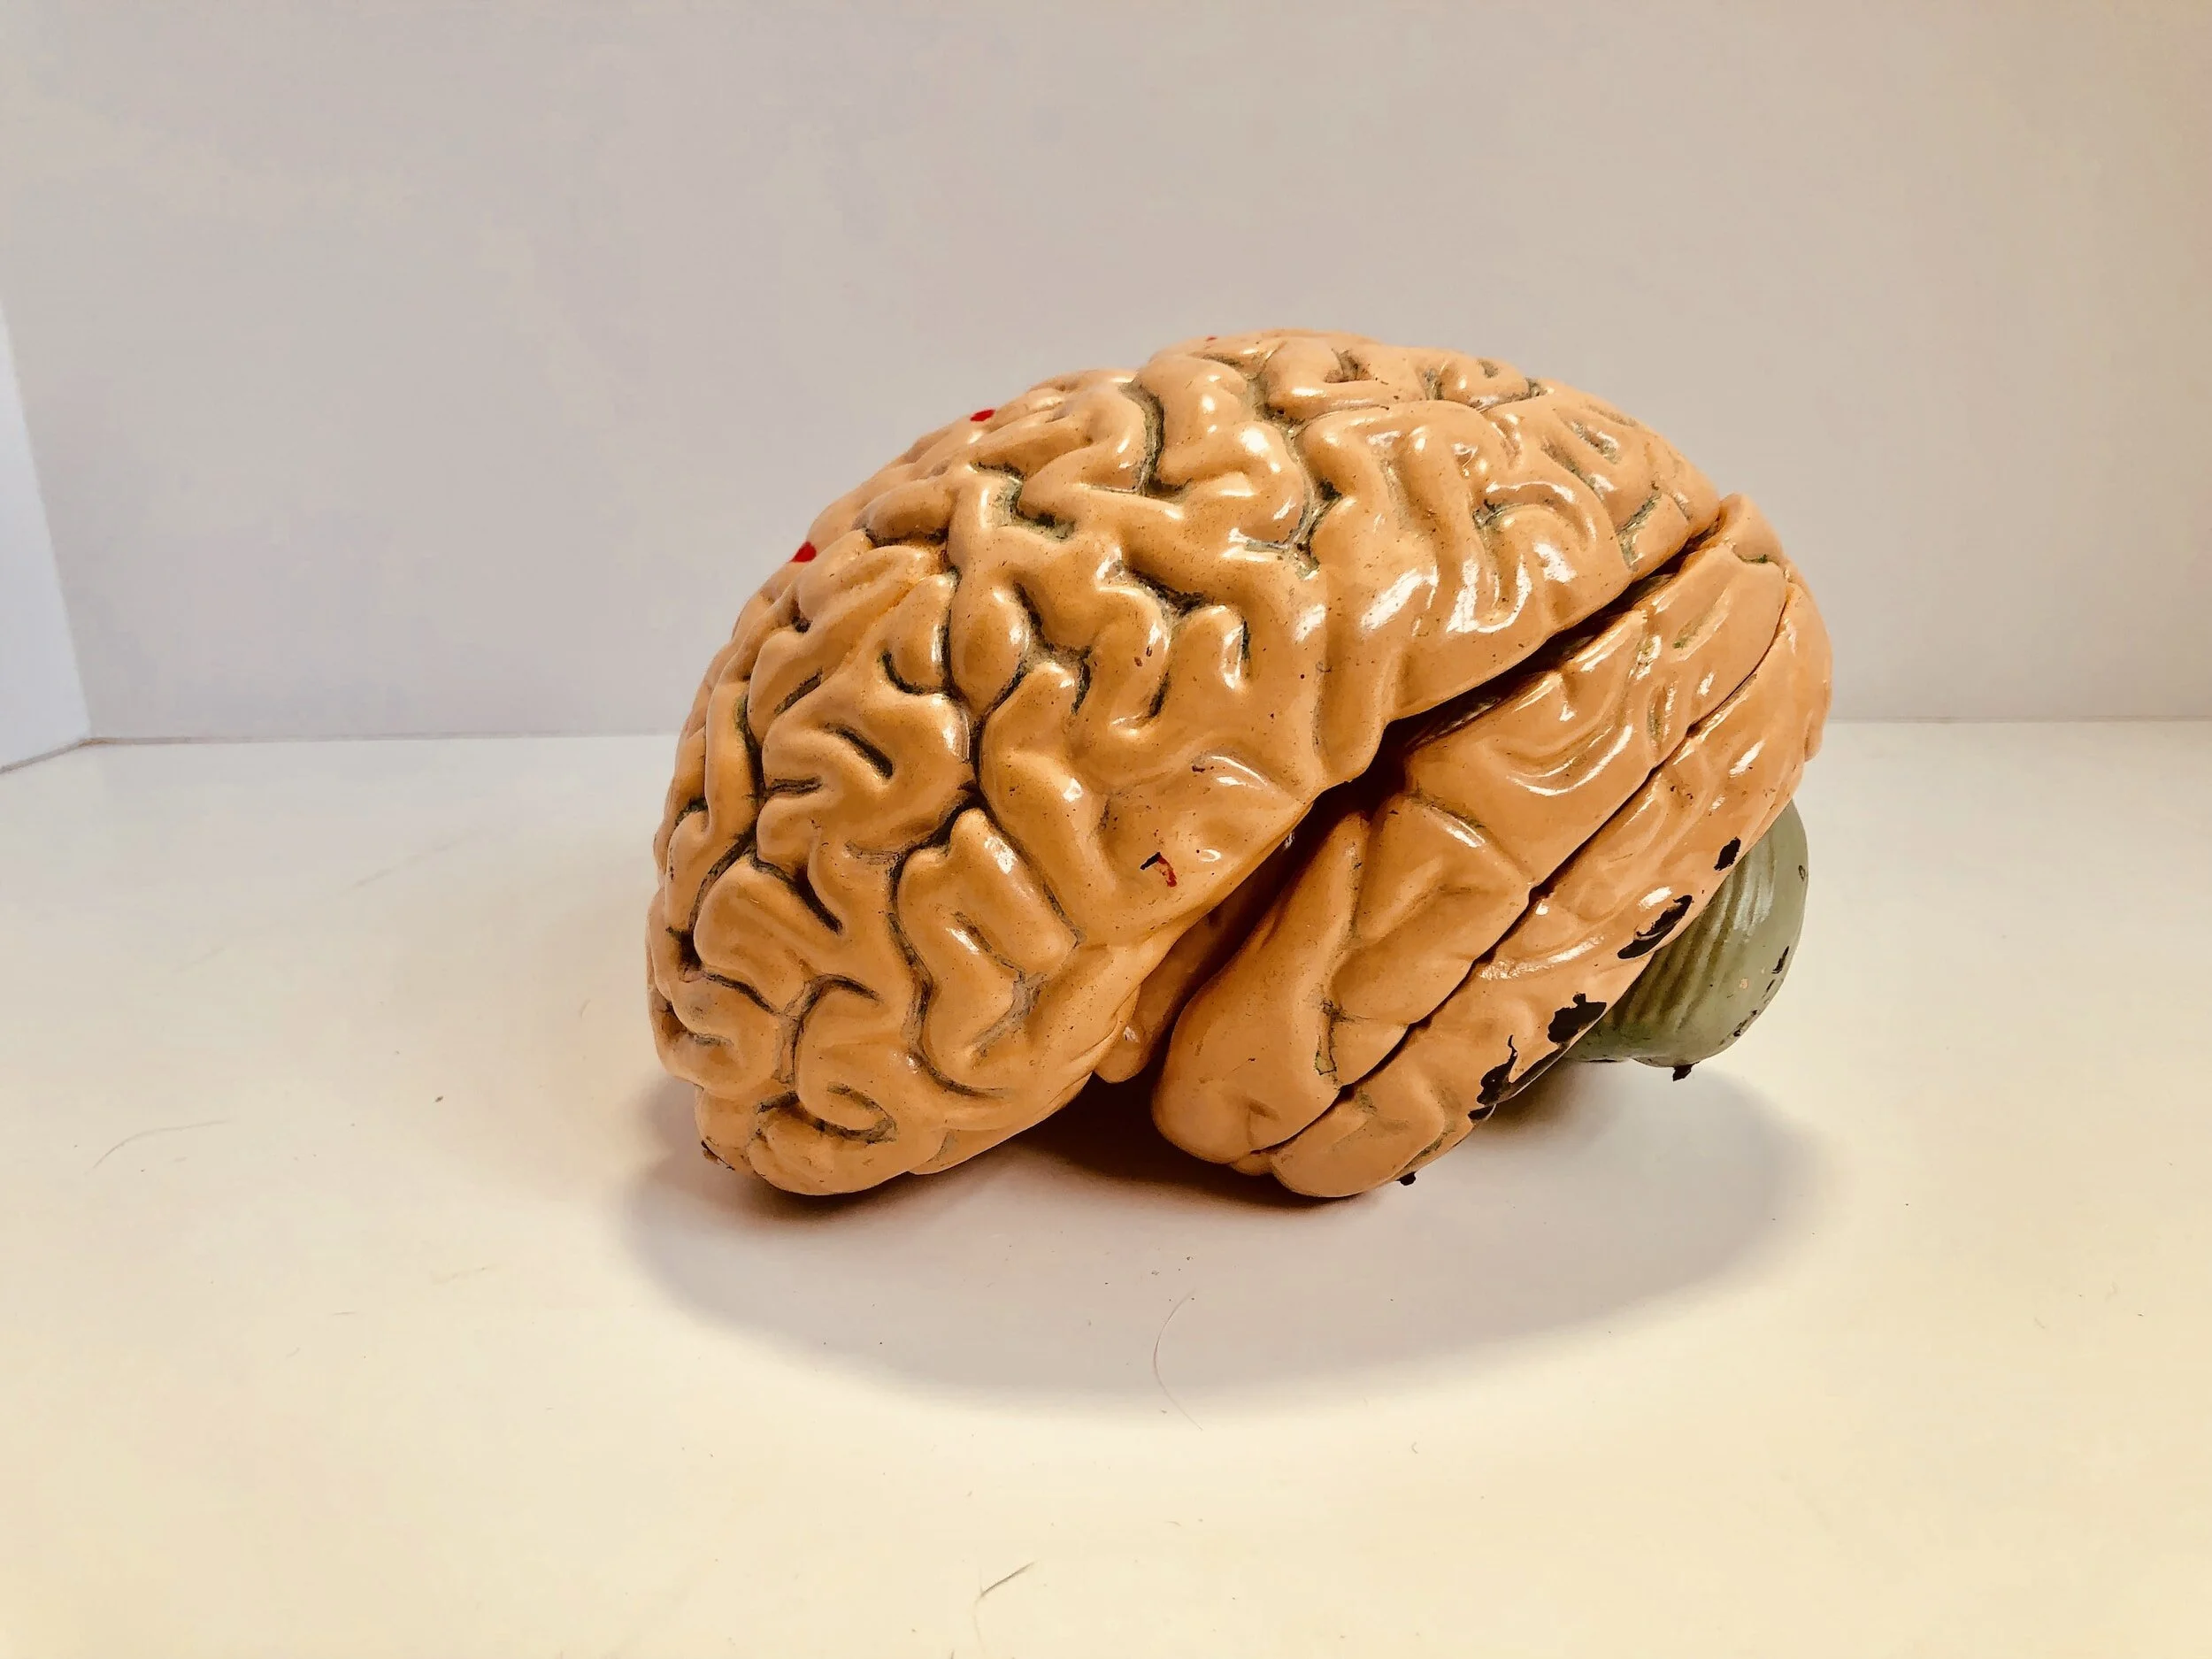

Prehospital and Emergency Care in Adult Patients with Acute Traumatic Brain Injury

La lesione cerebrale traumatica (TBI) è un problema sanitario di primaria importanza e un peso notevole per la società. L'identificazione di una TBI può essere difficile nel contesto pre-ospedaliero, in particolare nei pazienti anziani con cadute non osservate. Non è possibile escludere errori di triage sulla scena sulla base di una diagnostica clinica limitata. I potenziali nuovi strumenti diagnostici mobili potrebbero ridurre questi errori. L'assistenza preospedaliera comprende le decisioni relative ai percorsi clinici, ai mezzi di trasporto e al grado di trattamento preospedaliero. L'assistenza d'emergenza al momento del ricovero in ospedale comprende la diagnosi definitiva di TBI con o senza lesioni extracraniche e il triage verso la struttura ricevente appropriata per le cure definitive. I fattori di rischio precoci per un esito sfavorevole comprendono la gravità della TBI, la reazione della pupilla e l'età. Queste tre variabili sono fondamentali, incluse nella maggior parte dei modelli predittivi per la TBI, per prevedere la mortalità a breve termine. Altri fattori di rischio precoci di mortalità dopo TBI grave sono l'ipotensione e l'ipotermia. L'entità e la durata di questi due fattori di rischio possono essere ridotte con un'assistenza preospedaliera e di emergenza ottimale. Nuove potenziali vie di trattamento sono l'uso precoce di farmaci in grado di ridurre l'emorragia e l'edema cerebrale dopo la TBI. Ci sono ancora molte incertezze nell'assistenza preospedaliera e di emergenza per i pazienti con TBI, legate alla complessità dei modelli di TBI.